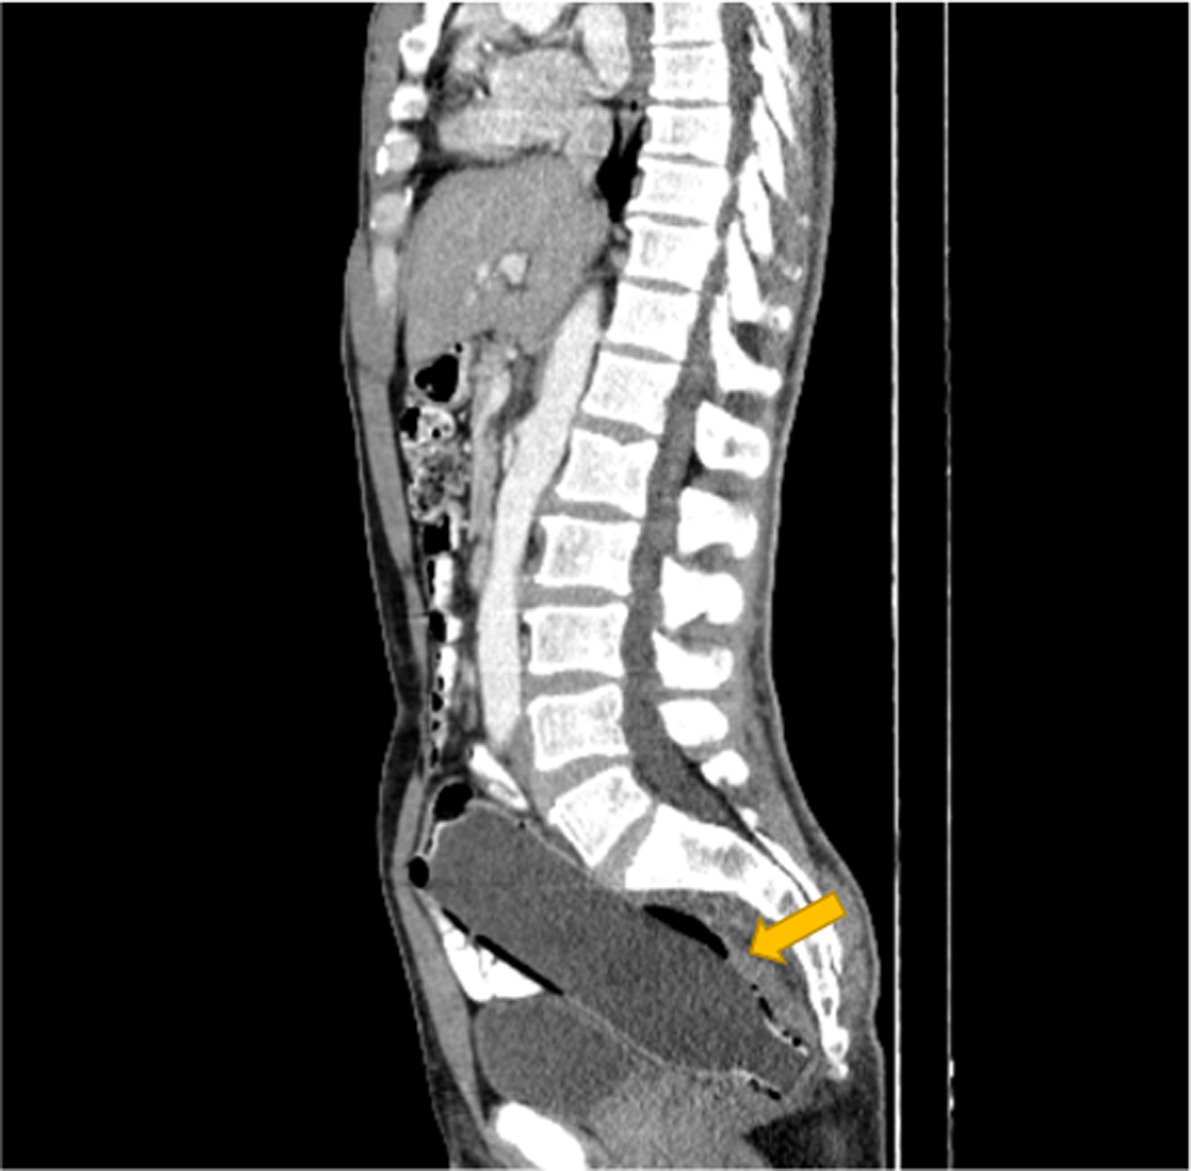

Ο άνδρας συνέχισε να κρύβει με επιτυχία το οδυνηρό μυστικό του, μέχρι που αποκαλύφθηκε στους γιατρούς μέσω αξονικής τομογραφίας.

Η μελέτη αναφέρει ότι είχε εισαγάγει το μπουκάλι με το κάτω μέρος να μπαίνει πρώτο, προκειμένου να χρησιμοποιήσει το επάνω μέρος ως λαβή για να το τραβήξει έξω.

Όταν όμως ήρθε η ώρα να γίνει αυτό, το αντικείμενο παγιδεύτηκε στο παχύ έντερο του άνδρα. Οι γιατροί στο νοσοκομείο Imam Khomeini στο Sari δεν ανέφεραν γιατί ακριβώς το μπουκάλι κόλλησε εκεί, αλλά είπαν ότι η σεξουαλική ικανοποίηση κρύβεται συνήθως πίσω από τέτοιου είδους καταστάσεις. Ο άνδρας ήταν επίσης γνωστό ότι είχε ιστορικό κατάθλιψης, σύμφωνα με το Clinical Case Reports.

Έκανε επείγουσα χειρουργική επέμβαση για την αφαίρεση του μπουκαλιού. Οι χειρουργοί κατάφεραν να τραβήξουν αργά το μπουκάλι προς τα έξω χωρίς να προκαλέσουν βλάβη στο έντερο.